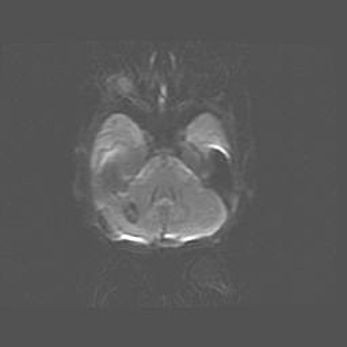

Мальформация Денди-Уокера. Киста задней черепной ямки.

Агенезия мозолистого тела.

Возраст: 2,5 месяца

Вес: 2420 г

Пол: женский

Окружность головы: 37 см

Срок гестации: 32 недели

Мальформация Денди—Уокера — редкий вид патологии ЦНС, представляющий собой врожденный порок развития каудального отдела ствола и червя мозжечка, ведущий к неполному раскрытию срединной (Мажанди) и латеральных (Лушка) апертур IV желудочка мозга. Для этогно синдрома характерна триада симптомов: гипотрофия червя мозжечка и/или полушарий мозжечка, кисты задней черепной ямки, гидроцефалия различной степени. В 70% случаев порок сочетается и с другими аномалиями головного мозга, в частности с агенезией мозолистого тела.